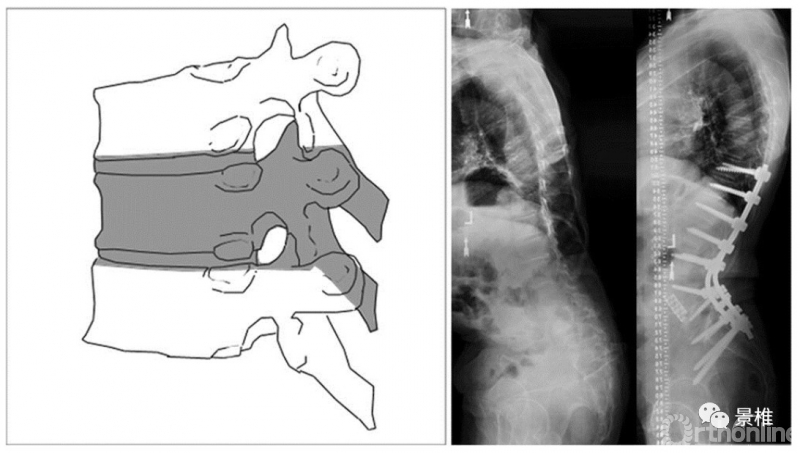

5级 VCR

5级,彻底拿掉一个椎体及上下间盘,在胸椎还包括同序列肋骨。一个椎体的叁柱全部切除了,所以也叫VCR(Vertebral Column Resection)。后凸矫形可达50º。

VCR简明图解:

VCR(vertebral column resection),椎体叁柱切除术。第一步,切除椎体后方结构。

如果在胸椎做VCR,还得把截骨椎两侧肋椎关节以及肋骨切除4-5cm,注意这一步胸膜不要被肋骨残端戳破。

截骨椎邻近节段“上叁下叁”置钉,一侧临时装棒固定。

椎板切除边界的简易确认方法:邻椎钉子的周围8mm左右。

胸段截骨时可以切断一侧或两侧神经根以增加显露视野。

断神经不要超过3个节段。腰段截骨禁止损伤神经根。

保护好脊髓,切除双侧椎弓根。切记椎弓根内侧操作时要格外小心胸段脊髓。

PSO操作类似,用叁角椎破除椎弓根,从椎弓根破处掏椎体。

胸段脊髓不能牵拉,需要显露侧方,从肋椎关节位置进入椎体。注意胸椎前、侧方毗邻的内脏和血管。

侧方椎体壁破除后,就可以一点点把椎体骨质掏干净了。

保持椎体前后壁完整,以免椎体过早闭合。开始切除上下椎间盘。

再小心切除硬膜囊腹侧周围的椎体后壁以及前壁,不要牵拉硬膜囊。椎体后壁残留最后一点切无可切时,利用高跟鞋敲击,使残留的后壁塌陷,清理之。

整体椎体结构都被拿掉了,体内原位折棒调整角度,凸侧加压、凹侧撑开复位脊柱序列。

椎间隙植入钛笼,硬膜囊上覆盖明胶海绵之类的保护下,把截除肋骨噼成条,做后方植骨。安装横联。